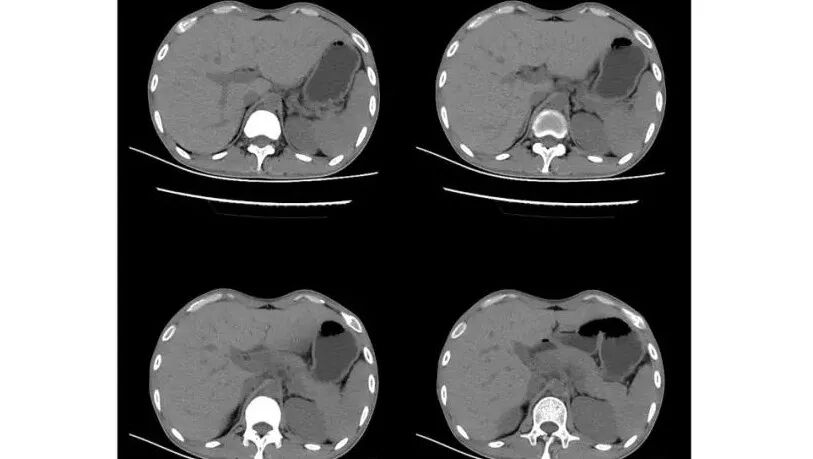

以下为2021-7-15日上腹部CT

影像与临床:1.青年男性,HlV阳性,颜面部皮疹(未提供皮疹图像)、发热(高热),实验室CRP、PCT高,T-Spot阴性。2.右肺下叶空洞结节,壁厚不均,边界清楚,其内线状影,未见液平及钙化,未见卫星灶,纵隔淋巴结增大,双侧腋窝见增大淋巴结。心腔内低密度提示贫血可能。肝脾影增大,未见结节影及块影。腹膜后见多发增大淋巴结。

综合分析:本例肺部影像学改变并不具有特征性,空洞性病灶须与多种疾病鉴别,但年轻HIV阳性患者,高热,皮疹,肝脾增大,纵隔、腋窝、腹膜后见多发增大淋巴结等都强烈提示马尔尼菲篮状菌感染的可能性。